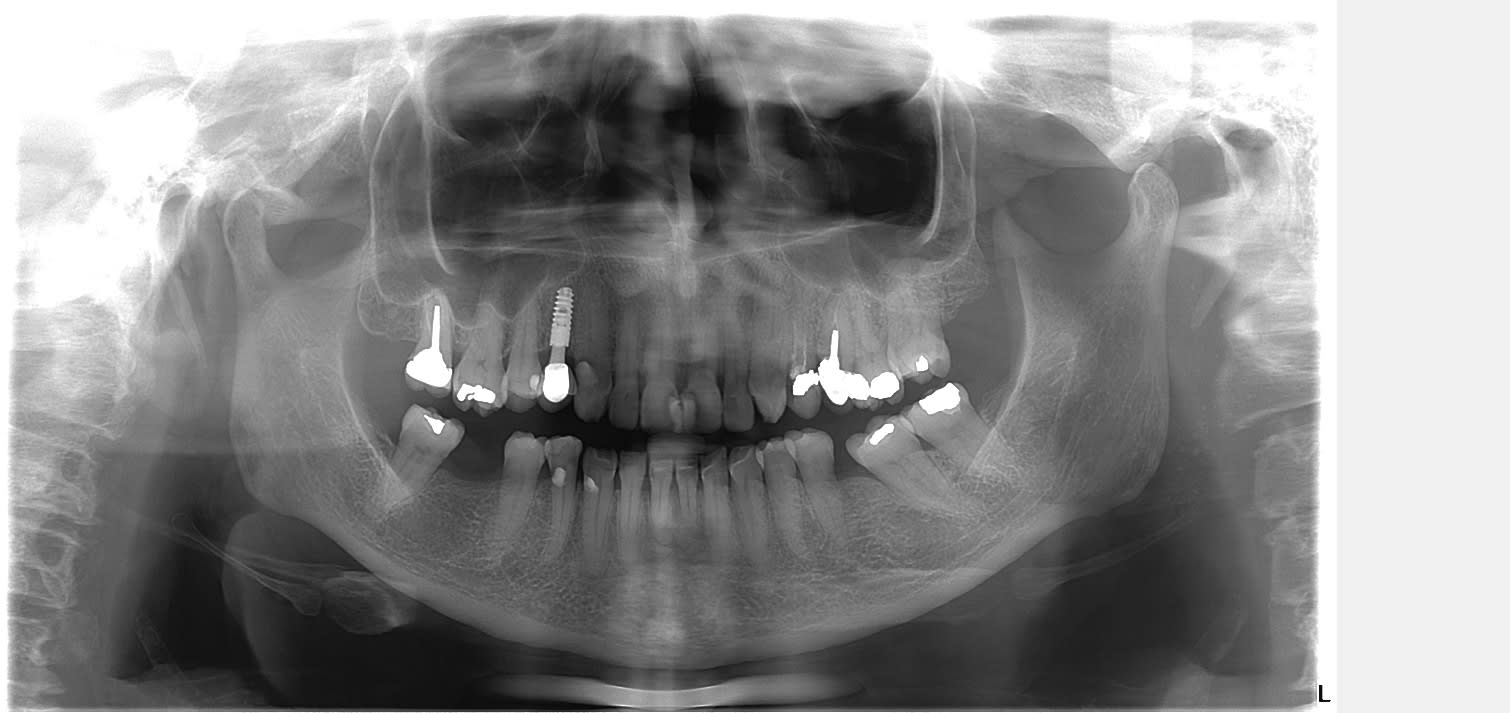

Nouvelle patiente 60 ans, pas de tabac, pas d'habitudes alimentaires prédisposantes mais syndrôme sec, très peu de salivation et ce depuis 2 ans.

A l'examen clinique, caries de collets typiques, la 45 a du être dévitalisée. Les caries sont plus importantes cliniquement que radiologiquement. Par ex les incisives mand étaient presque intégralement cariées en linguale (?).

Je lui ai fais un bilan et ai décidé de soigner les caries de collet au CVI (GC Equia forte). La 24 et 45 seront couronnées.